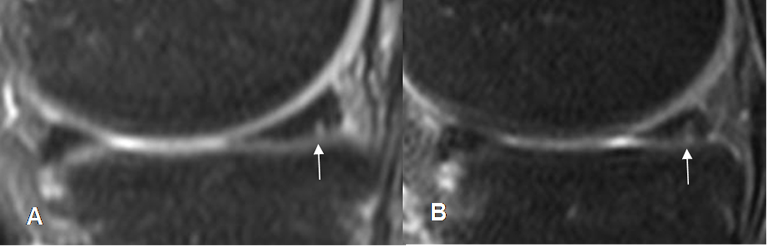

Fig 72. Ruptura meniscal vertical.

A y B: RM sagital en STIR. Imagen en sentido vertical que se comunica con la superficie articular inferior, por ruptura meniscal.